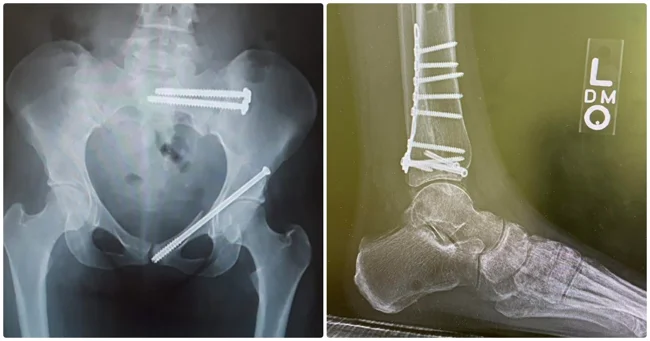

Слева - новое бедро

Таз после операции